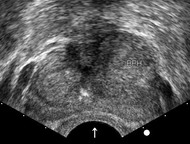

Transrectal ultrasound of prostate

Transrectal ultrasound showing prostate enlargement